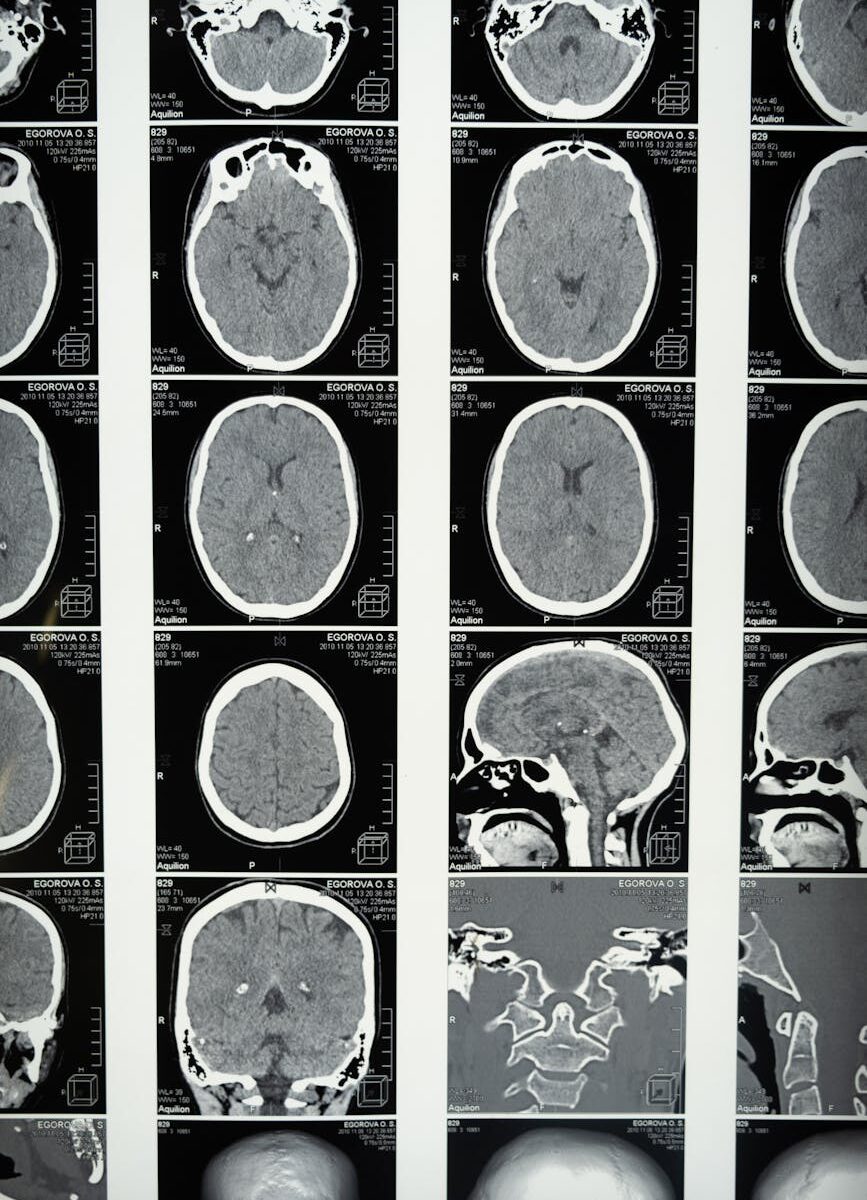

Onkologijoje AI sistemos analizuoja pacientų genetinius profilius ir siūlo personalizuotus gydymo planus. Viena mano pažįstama tyrinėtoja pasakojo, kaip jų laboratorijoje AI identifikavo naują vaisto kandidatą prieš agresyvią vėžio formą per šešis mėnesius – procesą, kuris tradiciniais metodais būtų užtrukęs penkerius metus ar ilgiau.